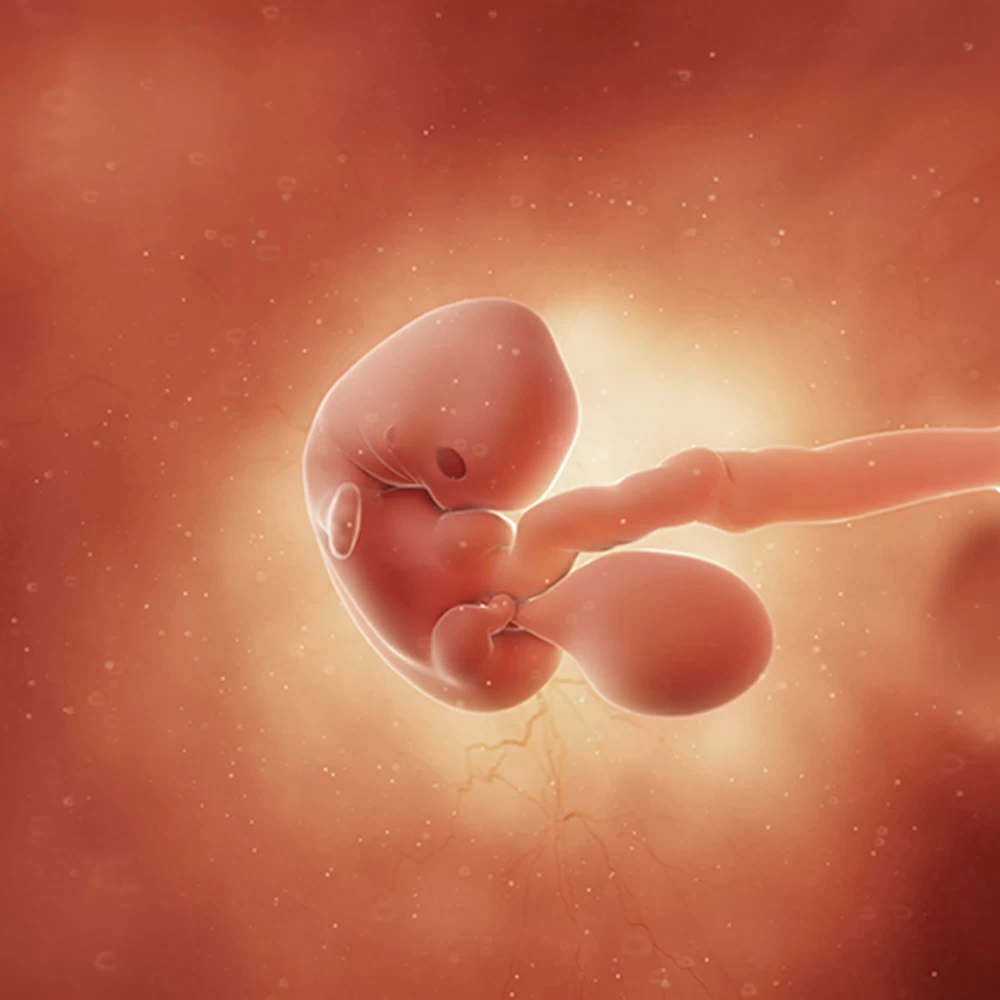

Беременность начинается с момента оплодотворения — слияния зрелой мужской клетки (сперматозоида) и женской яйцеклетки. В результате деления получается многоклеточный организм, который похож на ягоду ежевики (на латыни «морус»), отчего зародыш на этом этапе называют морулой. Приблизительно на 7 сутки происходит внедрение морулы в стенку матки (имплантация). Ворсинки внешних клеток зародыша соединяются с кровеносными сосудами матки, впоследствии из них образуется плацента.

Неделя № 2

Наружные клетки морулы плотно врастают в слизистую оболочку матки. У зародыша начинается формирование пуповины, плаценты, а также нервной трубки, из которой впоследствии развивается нервная система плода.